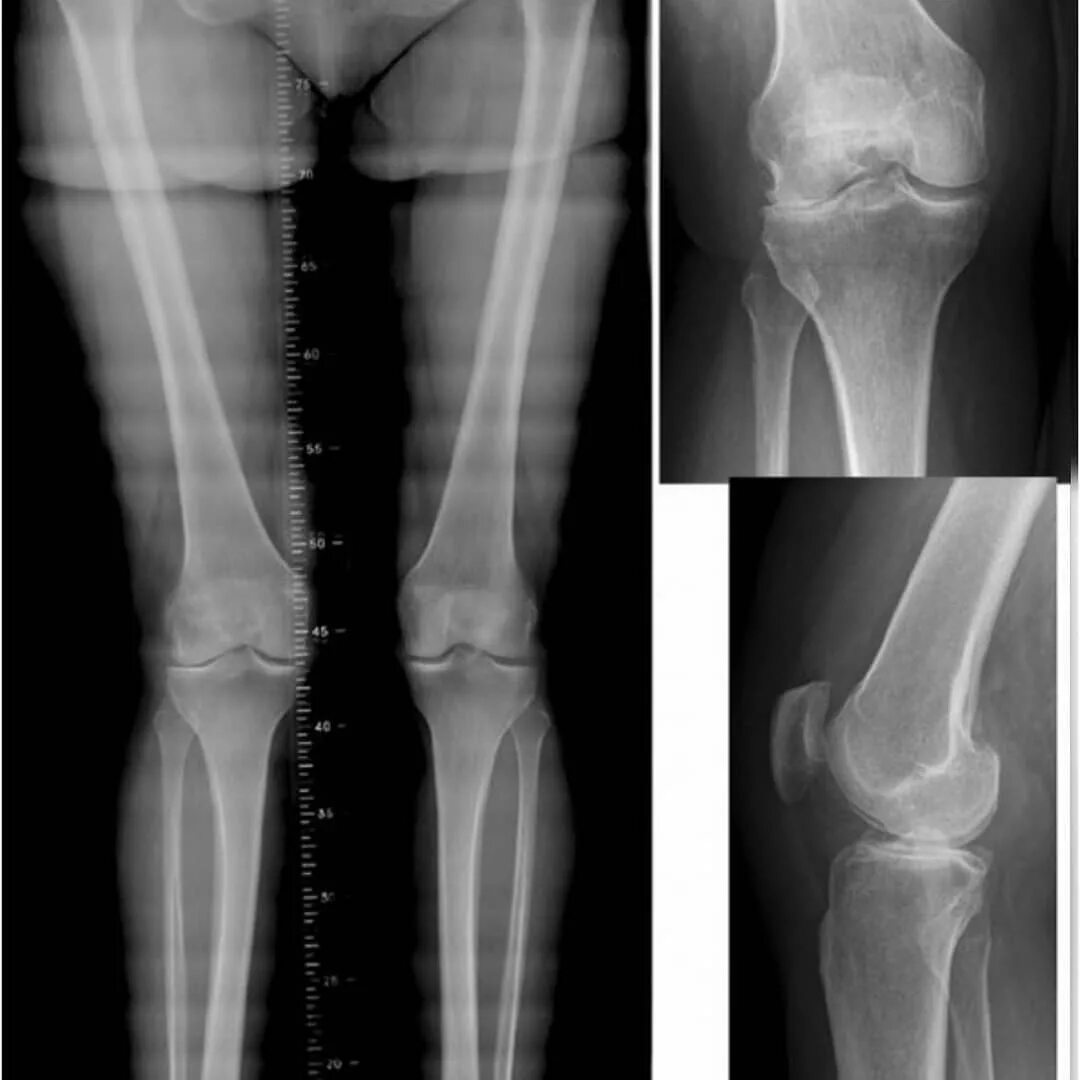

Деформация тазобедренного